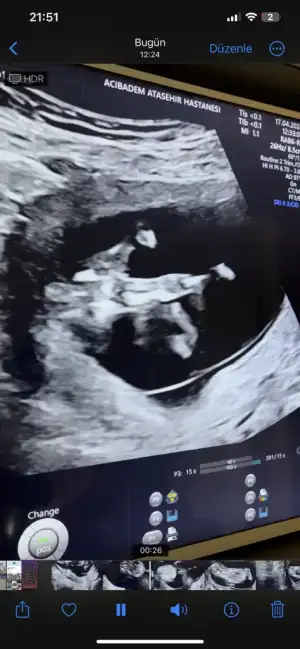

Kocaman olmus..🫶🩷 bakin bakalim cinsiyeti bilen var mi.bacaklari kapaliydi.. usg de anlayamayacaktik demek.dna testinde belli oldu.. su an ablam biliyor..benim.ogrenmem 1 ayi bulur sanirim... cenazemiz vardi..hemen kutlama yapamam . Annemde yok su an..onemi de yok aslinda..saglikli geldi ya sonuc. ☺️ zaten benim her seyimi gec ogrendim 🤣

Bacak arası yorum sizde